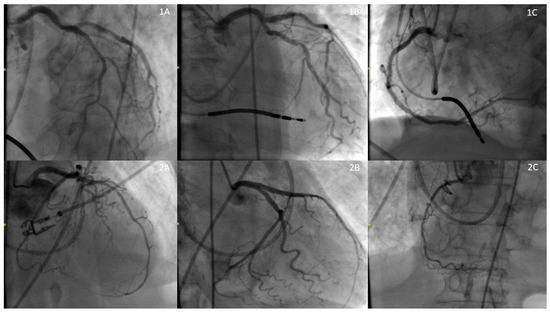

2.1. Case 1

2.2. Case 2